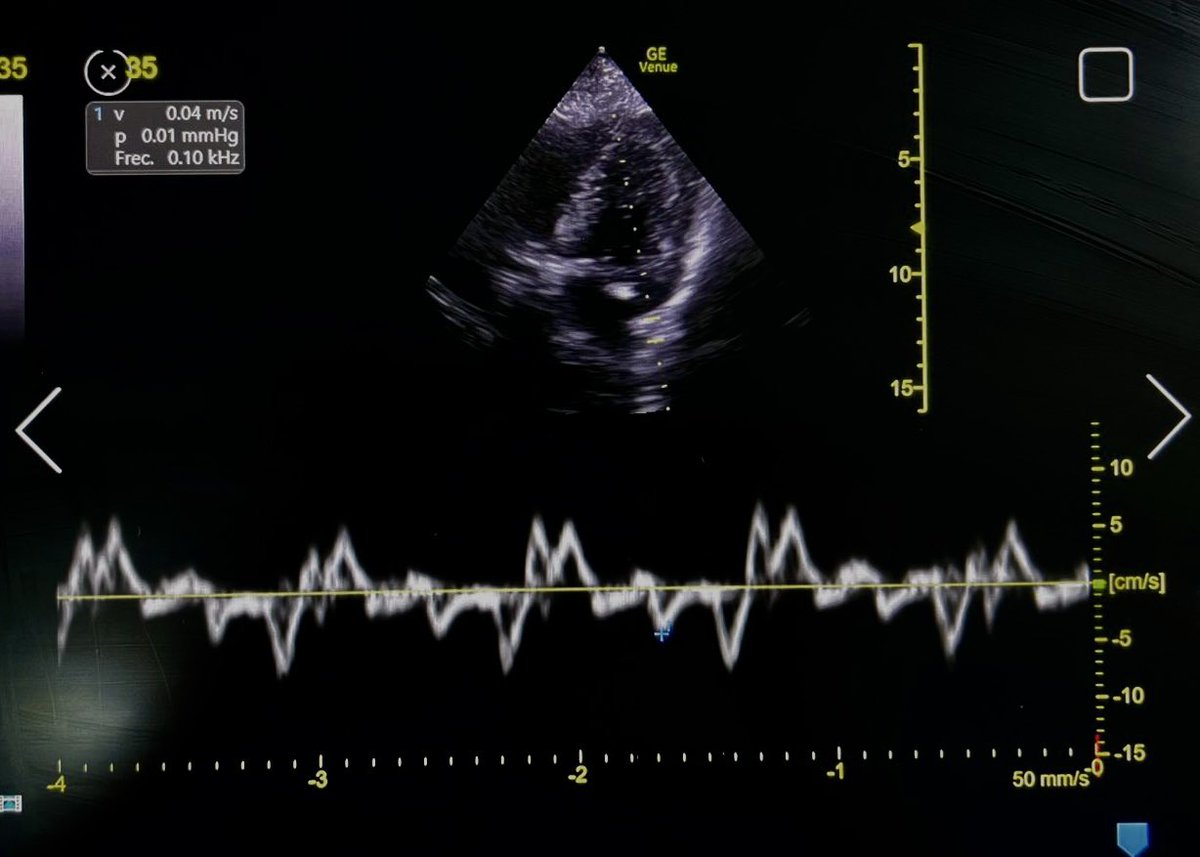

Plethoric IVC is likely due to IMV, this patient has low preload!

⬇️ preload can be caused by sepsis (venodilation/3rd spacing) or hypovolemia

#EchoFirst can't distinguish between these!

So, before giving fluid, it is wise to look for fluid tolerance 👇